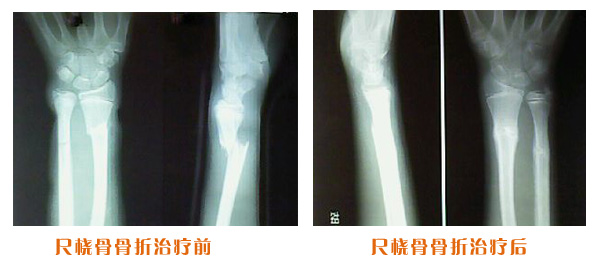

肥城市安駕莊梁氏骨科醫(yī)院是一所以梁氏手法正骨配合膏藥為特色的現(xiàn)代化專科醫(yī)院。

梁氏骨科術始創(chuàng)于清雍正年間,歷經(jīng)八代,至今已有三百年歷史。據(jù)1929年泰安縣志載“梁瑞圖先生,字增生,號蓮峰,安駕莊人,精岐黃并發(fā)明接骨,凡跌打車凡跌打車軋皮不破而碎骨者......【詳細】 |